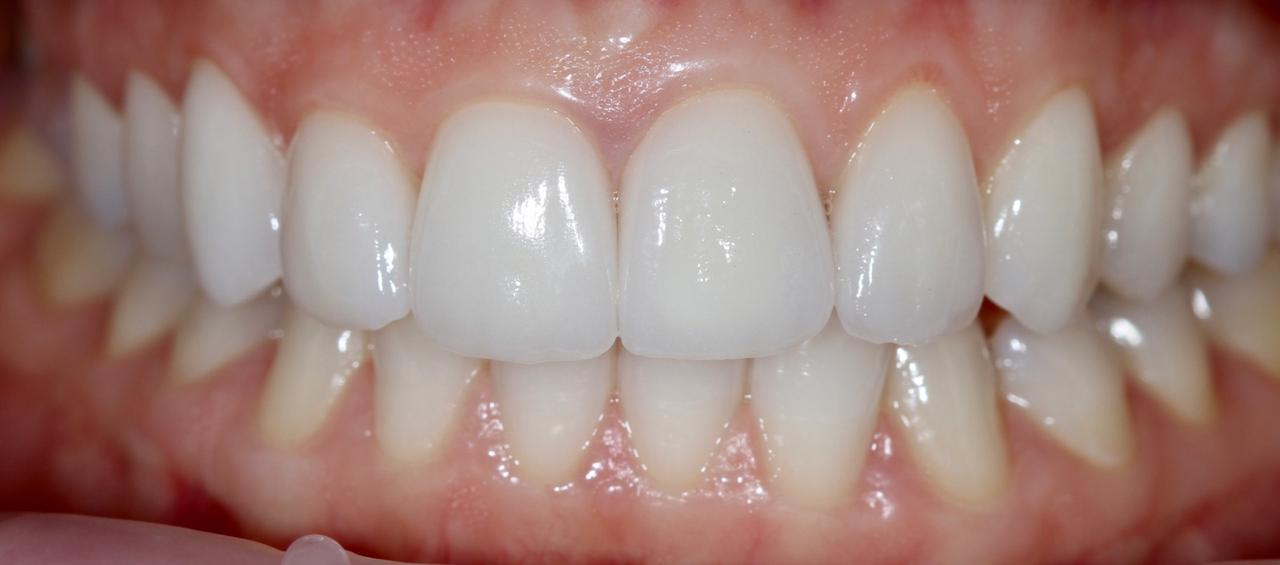

Белые виниры BLEACH

Все чаще стали поступать заказы на виниры цвета BLEACH. Очень красивый результат. Улыбка становится очень красивой.

Это виниры на рефракторе . 12 зуб коронка на оксиде циркония.